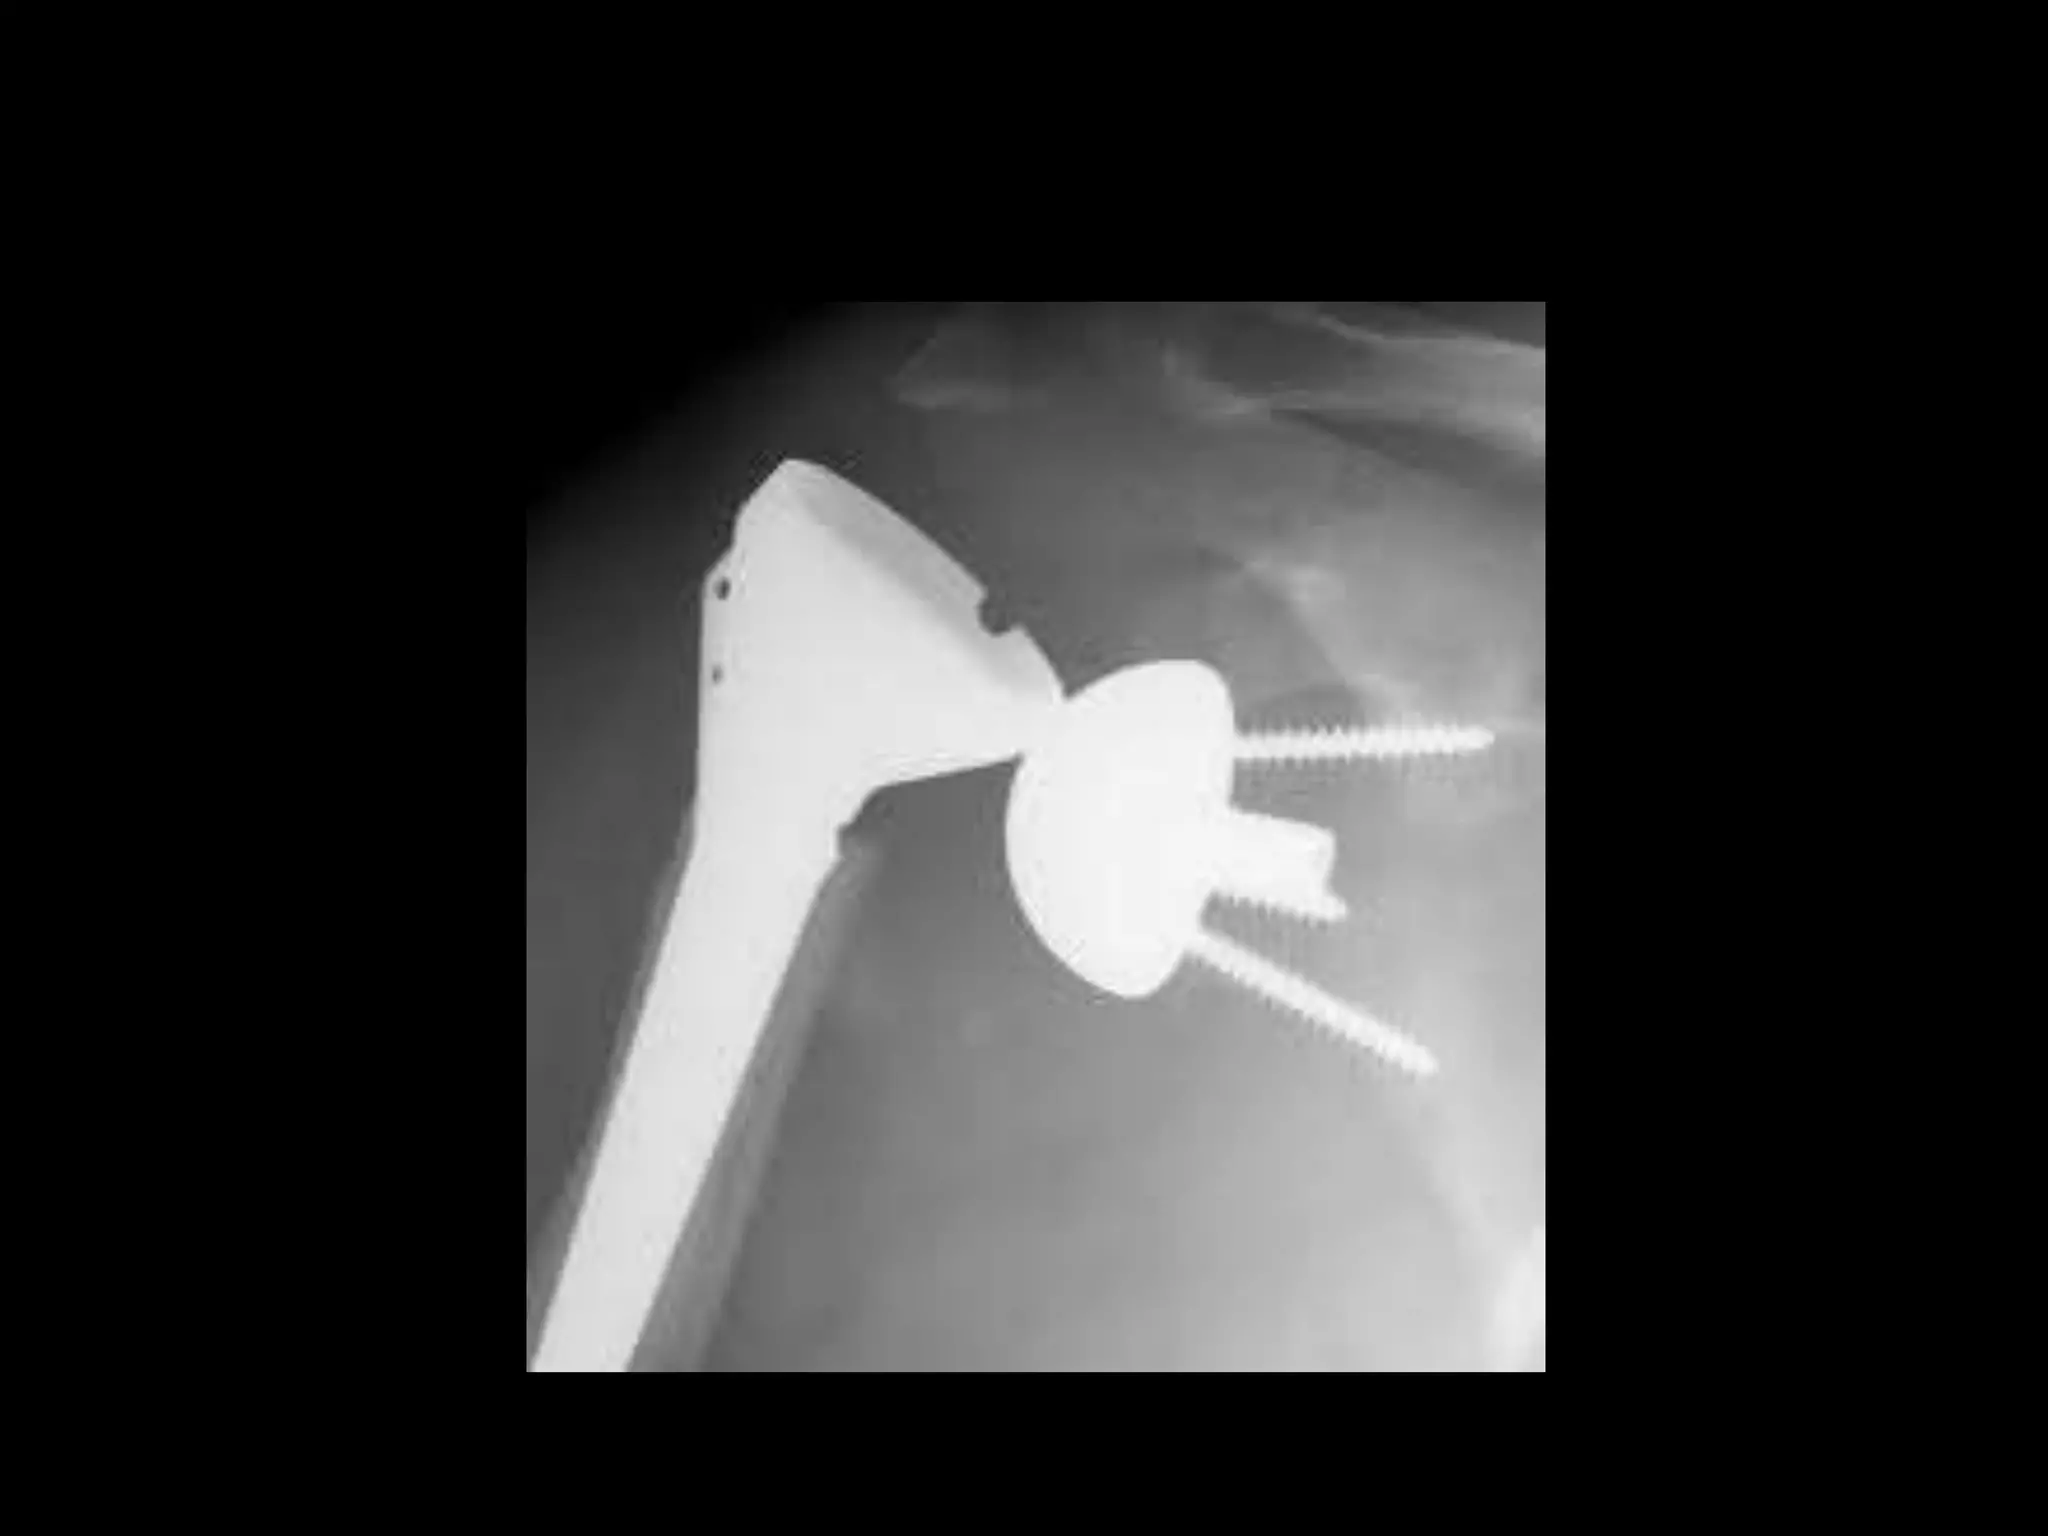

Grammont Type Reverse

(France 1987)

Grammont P, Trouilloud P, Laffay JP, et al. Etude et realisation d’unenouvelle

prothe`sed’e`paule.Rheumatologie. 1987;39:407–418. [French]

Grammont Type Reverse (France1987) Grammont P, Trouilloud P, Laffay JP, et al. Etude et realisation d’unenouvelle prothe`sed’e`paule.Rheumatologie. 1987;39:407–418. [French]